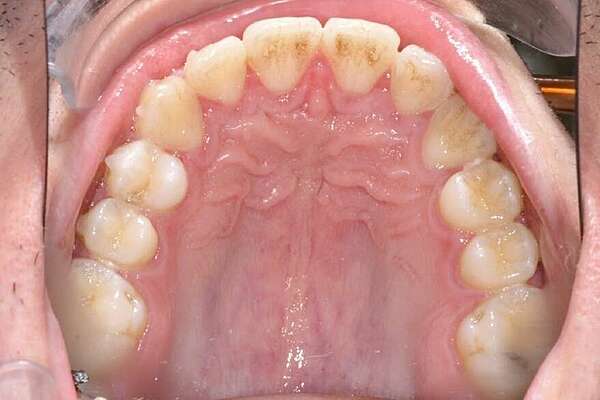

Important encombrement traité par gouttières